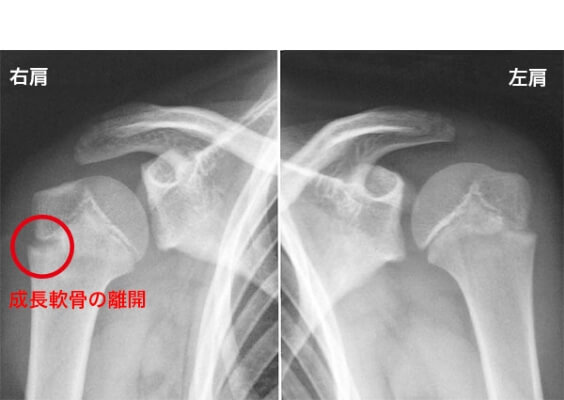

3.リトルリーグショルダー(上腕骨骨端線離開)

成長期の投球障害で、投球時や投球後に肩の痛みを訴えます。子どもの骨の端の方には骨を形成する細胞が密集する成長線という軟骨(成長軟骨)がありますが、骨に比べて強度が弱く、過度の投球による負荷で損傷し、上腕骨の肩の部分の成長軟骨(骨端線)の離開(骨端線離開)が起こって痛みが表れるスポーツ障害です。放置しておくと痛むだけでなく成長障害にも繋がる可能性もあります。投球動作の他、ラケット競技、あるいは転倒した際に肩から落ちるなどの外傷が、その原因として挙げられます。

投球時に痛み、投球後に痛み、肩をねじると痛みが出ます。